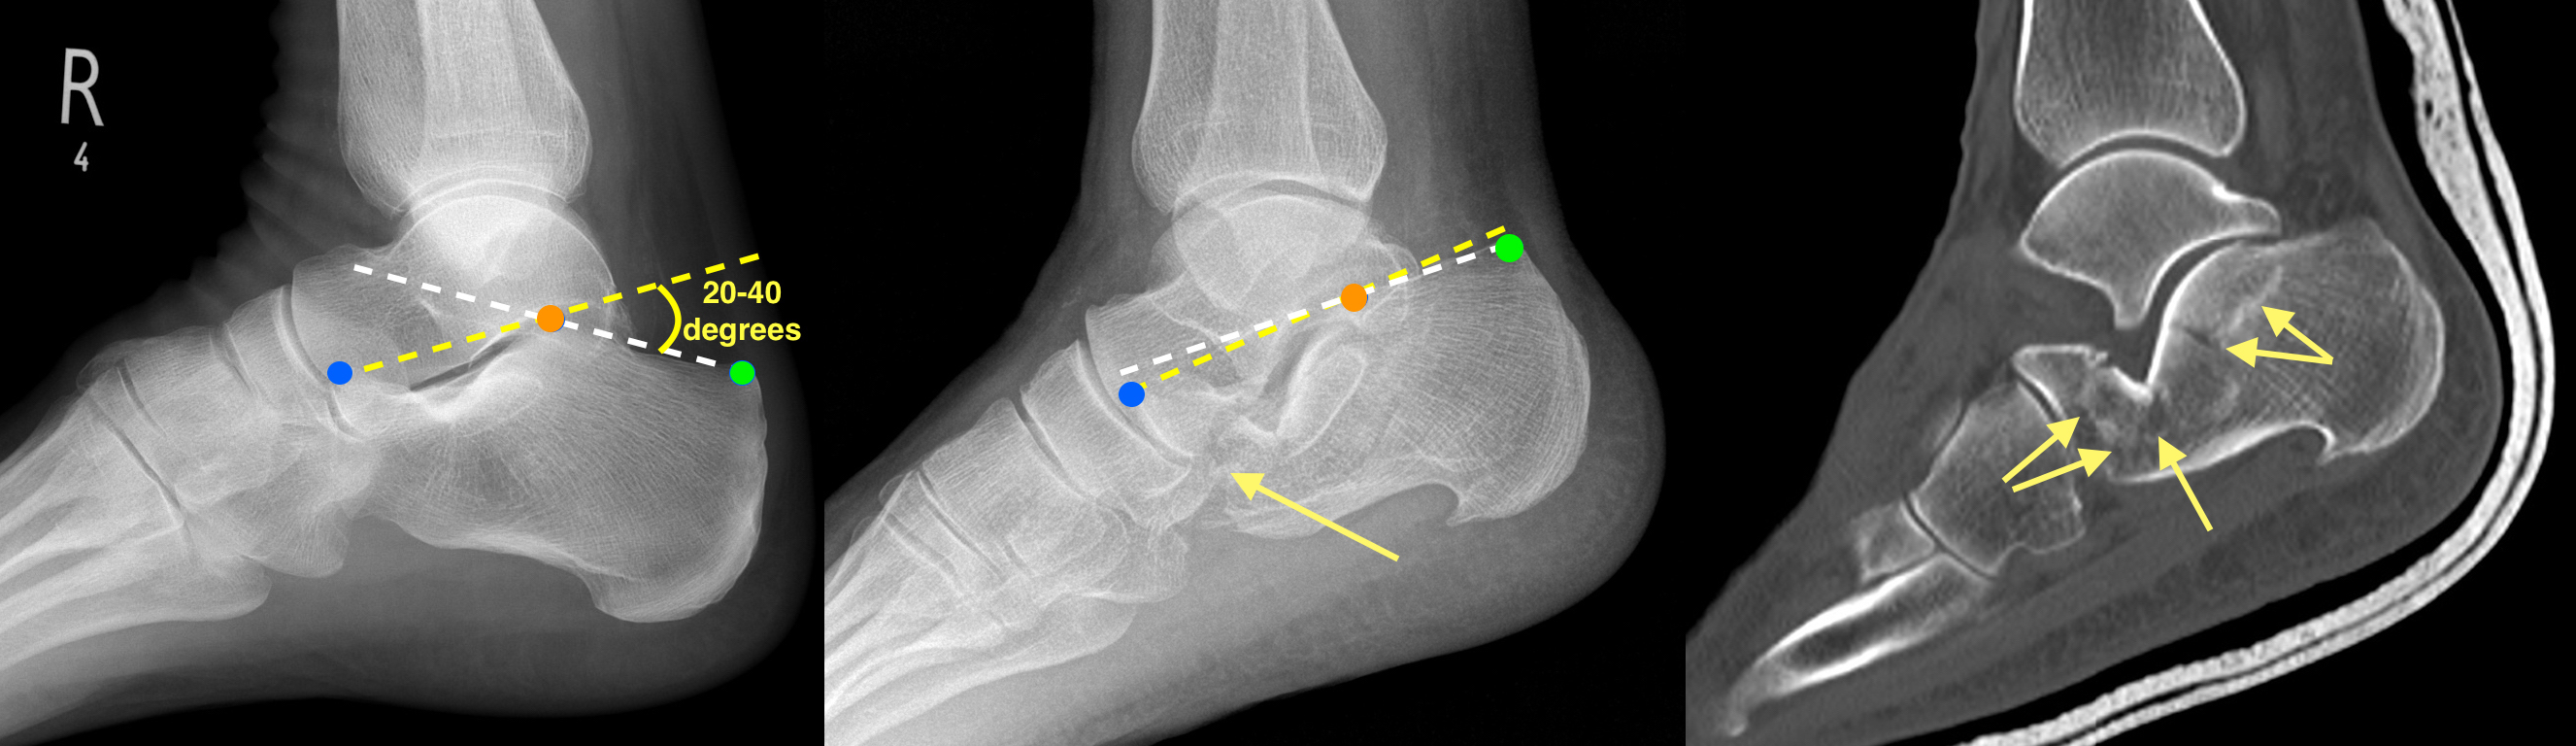

Calcaneal Fractures and Böhler’s Angle JETem Calcaneus X Ray Angle Böhler angle is a measure of the calcaneal tuberosity and articular facet on a lateral foot radiograph. It does not mention bohler angle, a radiographic. A study of 24 healthy feet to quantify the normal foot and ankle angles, measures, and reference points from ap, lateral, and axial views. The data provide a set of standard foot and ankle measures. Calcaneus X Ray Angle.

From jetem.org

Calcaneal Fractures and Böhler’s Angle JETem Calcaneus X Ray Angle A study of 24 healthy feet to quantify the normal foot and ankle angles, measures, and reference points from ap, lateral, and axial views. The data provide a set of standard foot and ankle measures and nomenclature for preoperative planning and intraoperative and postoperative evaluations. This web page covers the epidemiology, anatomy, classification, presentation, imaging, and treatment of calcaneus fractures.. Calcaneus X Ray Angle.

Anatomy Critical Angle of Gissane for Calcaneus Fractures Radiology Calcaneus X Ray Angle This web page covers the epidemiology, anatomy, classification, presentation, imaging, and treatment of calcaneus fractures. A study of 24 healthy feet to quantify the normal foot and ankle angles, measures, and reference points from ap, lateral, and axial views. It does not mention bohler angle, a radiographic. Böhler angle is a measure of the calcaneal tuberosity and articular facet on. Calcaneus X Ray Angle.